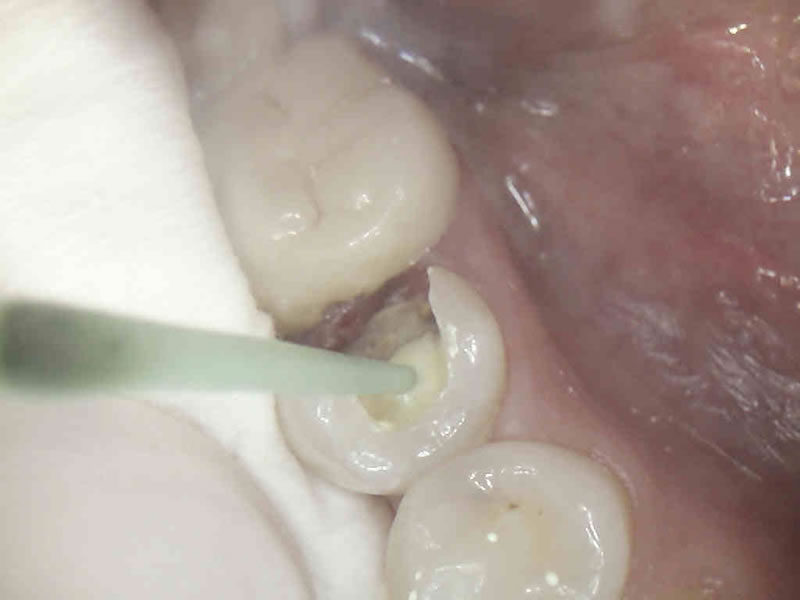

Svima dobro poznati, sivi, amalgamski ispuni, danas se iz zdravstvenih i estetskih razloga zamjenjuju estetskim, kompozitnim ispunima.

Naša su iskustva u praksi da redovno, ispod amalgamskog ispuna, u toku sanacije zuba pronalazimo karijes. Obrazloženje je u činjenici da se amalgam kao materijal za ispun s vremenom skvrčava i time stvara pukotinu između sebe i stjenke zuba. To naravno dovodi do prodora bakterija karijesa u kavitet na zubu a time i kvarenja zuba.

Estetski ( bijeli ) materijali ne mijenjaju volumen tijekom vremena. Dakle, nema pukotine, nema prodora bakterija i nema kvarenja zuba.

Postavljanjem estetskog materijala postižemo kvalitetnu rekonstrukciju zubnog tkiva i potpuno prirodan izgled za razliku od ( sivog, metalnog ) amalgamskog ispuna.

Za izradu estetskog ispuna potrebno je odstraniti samo bolestan dio zuba za razliku od amalgamskog ispuna za koji je bilo potrebno odstraniti i dio zdravog zubnog tkiva zbog držanja amalgama u zubu.